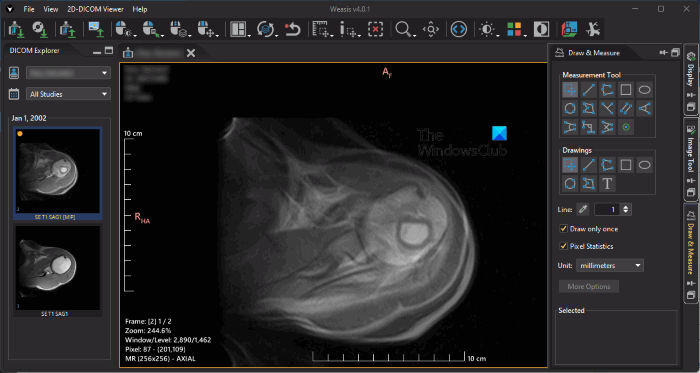

3] Weasis

Weasis is a free medical image viewer software that lets you open DICOM files and images in other formats. To open a DICOM file, go to “File > Open > DICOM.” If you want to open the image files in the formats other than DICOM, go to “File > Open > Image.” You can also import the DICOM files from DICOM CD by using the Import option.

Weasis has multiple language support. The default language is English. To change your language, go to “File > Preferences” or press the Alt + P keys. You will see three tabs on the right side, namely Display, Image Tool, and Draw & Measure.

- Display: The Display tab lets you show and hide DICOM images, annotations, scale, drawings, etc.

- Image Tool: This tab lets you change the properties of the DICOM file. You can change the image rendering level by moving the slider, change LUT shapes, select different LUTs for the DICOM file, rotate the DICOM image, etc.

- Draw & Measure: This tab has annotation and measurement tools. In addition to this, you can also change the unit of measurement. By default, the unit of measurement is set to millimeters.

You can export the DICOM files into PNG, JPEG, and TIFF image formats. You can download it from sourceforge.net.